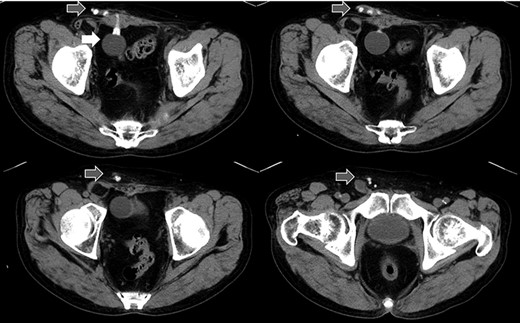

Abdominal CT in Case 1: CT showed that there was a balloon nearby the bladder and the tube went beside the rectus abdominis muscle from abdominal cavity; balloon, white arrow; tubes, gray arrows.

A 79-year-old male was referred to our institute for the treatment of right IH. He had received AUS implantation for the treatment of incontinence after RP for prostate cancer. Abdominal

Abdominal US image in Case 1: US showed the tubes running under the aponeurosis of the external oblique that is the anterior wall of the inguinal canal.

computed tomography (CT) showed right IH and a balloon that was placed by the bladder and a connecting catheter that went through the lateral side of the rectus abdominis muscle (Fig. 2). In the operation, we performed ultrasonography (US) at first and it demonstrated that the catheter was running through the inguinal canal (Fig. 3). When we incised the aponeurosis of the external abdominal oblique muscle, the catheter of the AUS was observed in the inguinal canal (Fig. 4). We identified the hernia sac protruding from the inguinal ring and diagnosed it as an indirect IH. The adhesion was too hard to separate the catheter from the pubis and posterior wall of the inguinal canal around pubis. Then, the IH was repaired using the Lichtenstein technique; however, the mesh near the pubis could not be spread as ordinarily.